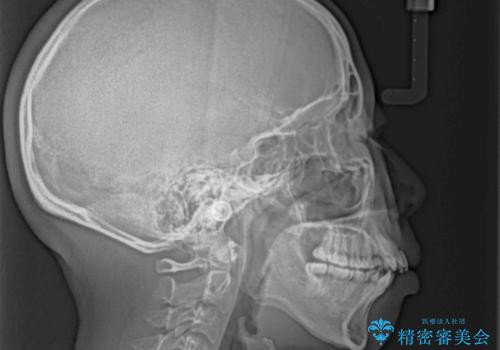

- 八重歯と、上下前歯が接触しないくらい前突した前歯を気にして来院された患者様です。

奥歯の噛み合わせは正常に近い状態でしたが、右上の奥歯に突起があったり、上下前歯が非接触であったりしていたため、補助装置を使用して上顎前歯を積極的に引っ込めるように計画しました。

口元の突出感を改善するために上下左右の小臼歯4本を抜歯し、ワイヤー装置によりデコボコを解消しながら口元の突出感も改善していくこととしました。

上下の前歯が接触する仕上がりとなったので、横顔の印象が大幅に改善されました。